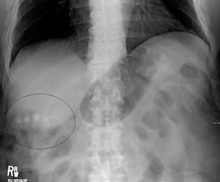

Images of a CT of gallstones